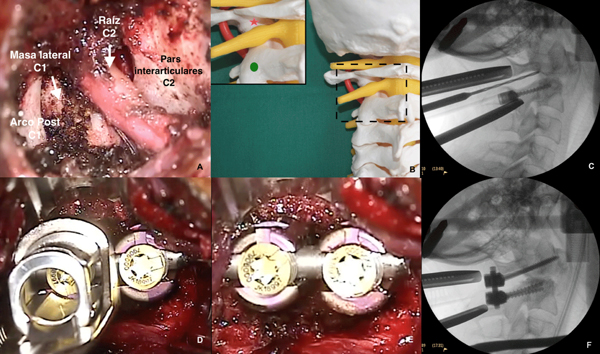

Una vez lograda la exposición ósea deseada (Figura 6A) y localizado el punto de ingreso de los tornillos en la masa lateral de C1 y en la pars interarticularis de C2 (Figura 6B); y antes de proceder con la colocación de los mismos, se deben decorticar las superficies óseas para favorecer la artrodesis con los chips óseos que se colocaran a posteriori, ya que una vez colocado el material protésico no queda espacio suficiente para poder realizar esta maniobra.

Figura 6. Artrodesis instrumentada posterior C1-C2.

A. Exposición intraoperatoria. B. Representación en maqueta del punto de entrada de los tornillos en la masa lateral de C1 (estrella) y en la pars interarticularis de C2 (círculo). C. Radioscopía intraoperatoria durante el fresado de la dirección del tornillo de C1. D. Imagen intraoperatoria: el campo quirúrgico permite la utilización de todos los instrumentos requeridos para la correcta colocación de los tornillos y barras. E. y F. Imagen final intraoperatoria de la lodge (E.) y de radioscopía (F.) con los tornillos y barras colocadas.

Artrodesis instrumentada

A continuación, se colocan los tornillos poliaxiales en C1 y C2 según la técnica de Harms (Figura 6C-F), utilizándose tornillos con rosca parcial o vástago en C1 y teniendo en cuenta que para lograr la trayectoria adecuada en el tornillo del axis, es necesario angular levemente el separador hacia cefálico. La artrodesis se completa con la colocación de la barra y sustituto óseo lateral a la misma.